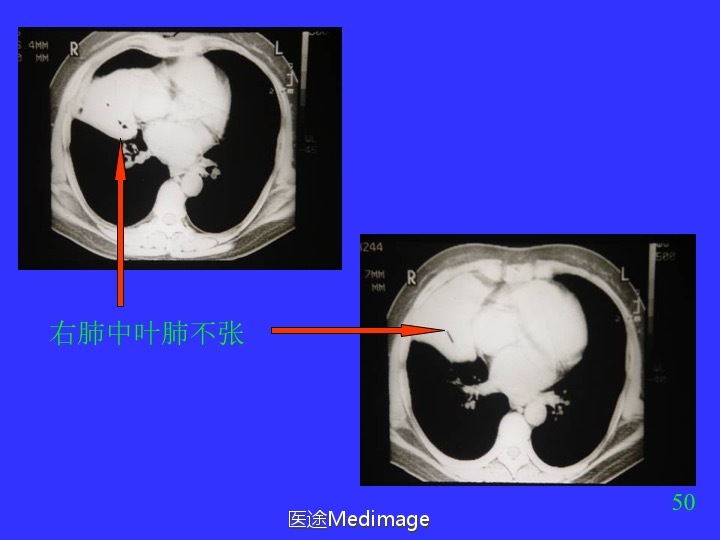

胸部CT阅读与诊断(三)各种肺不张